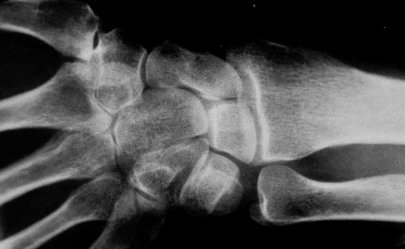

Standard Xray view: PA wrist

Xray beam angle 90 degrees.